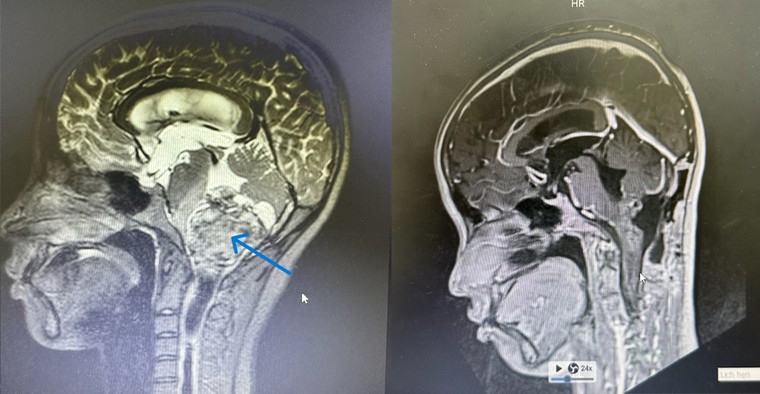

Hình ảnh chụp khối u ở vị trí thân não (bên trái) và sau khi khối u được phẫu thuật loại bỏ (bên phải).Ảnh: BVĐK Tâm Anh. |

Bác sĩ Chu Tấn Sĩ cho biết, khối u khoảng 6x5 cm ở thân não của người bệnh chèn ép đường dẫn truyền thần kinh vận động, vị trí rất khó phẫu thuật, dễ làm tổn thương các chức năng thần kinh sau mổ. Nếu mổ bằng các phương pháp truyền thống khó đánh giá và bảo toàn các bó sợi thần kinh. Chỉ cần một sai lầm nhỏ, bệnh nhân sẽ yếu liệt vĩnh viễn hoặc mất tính mạng.